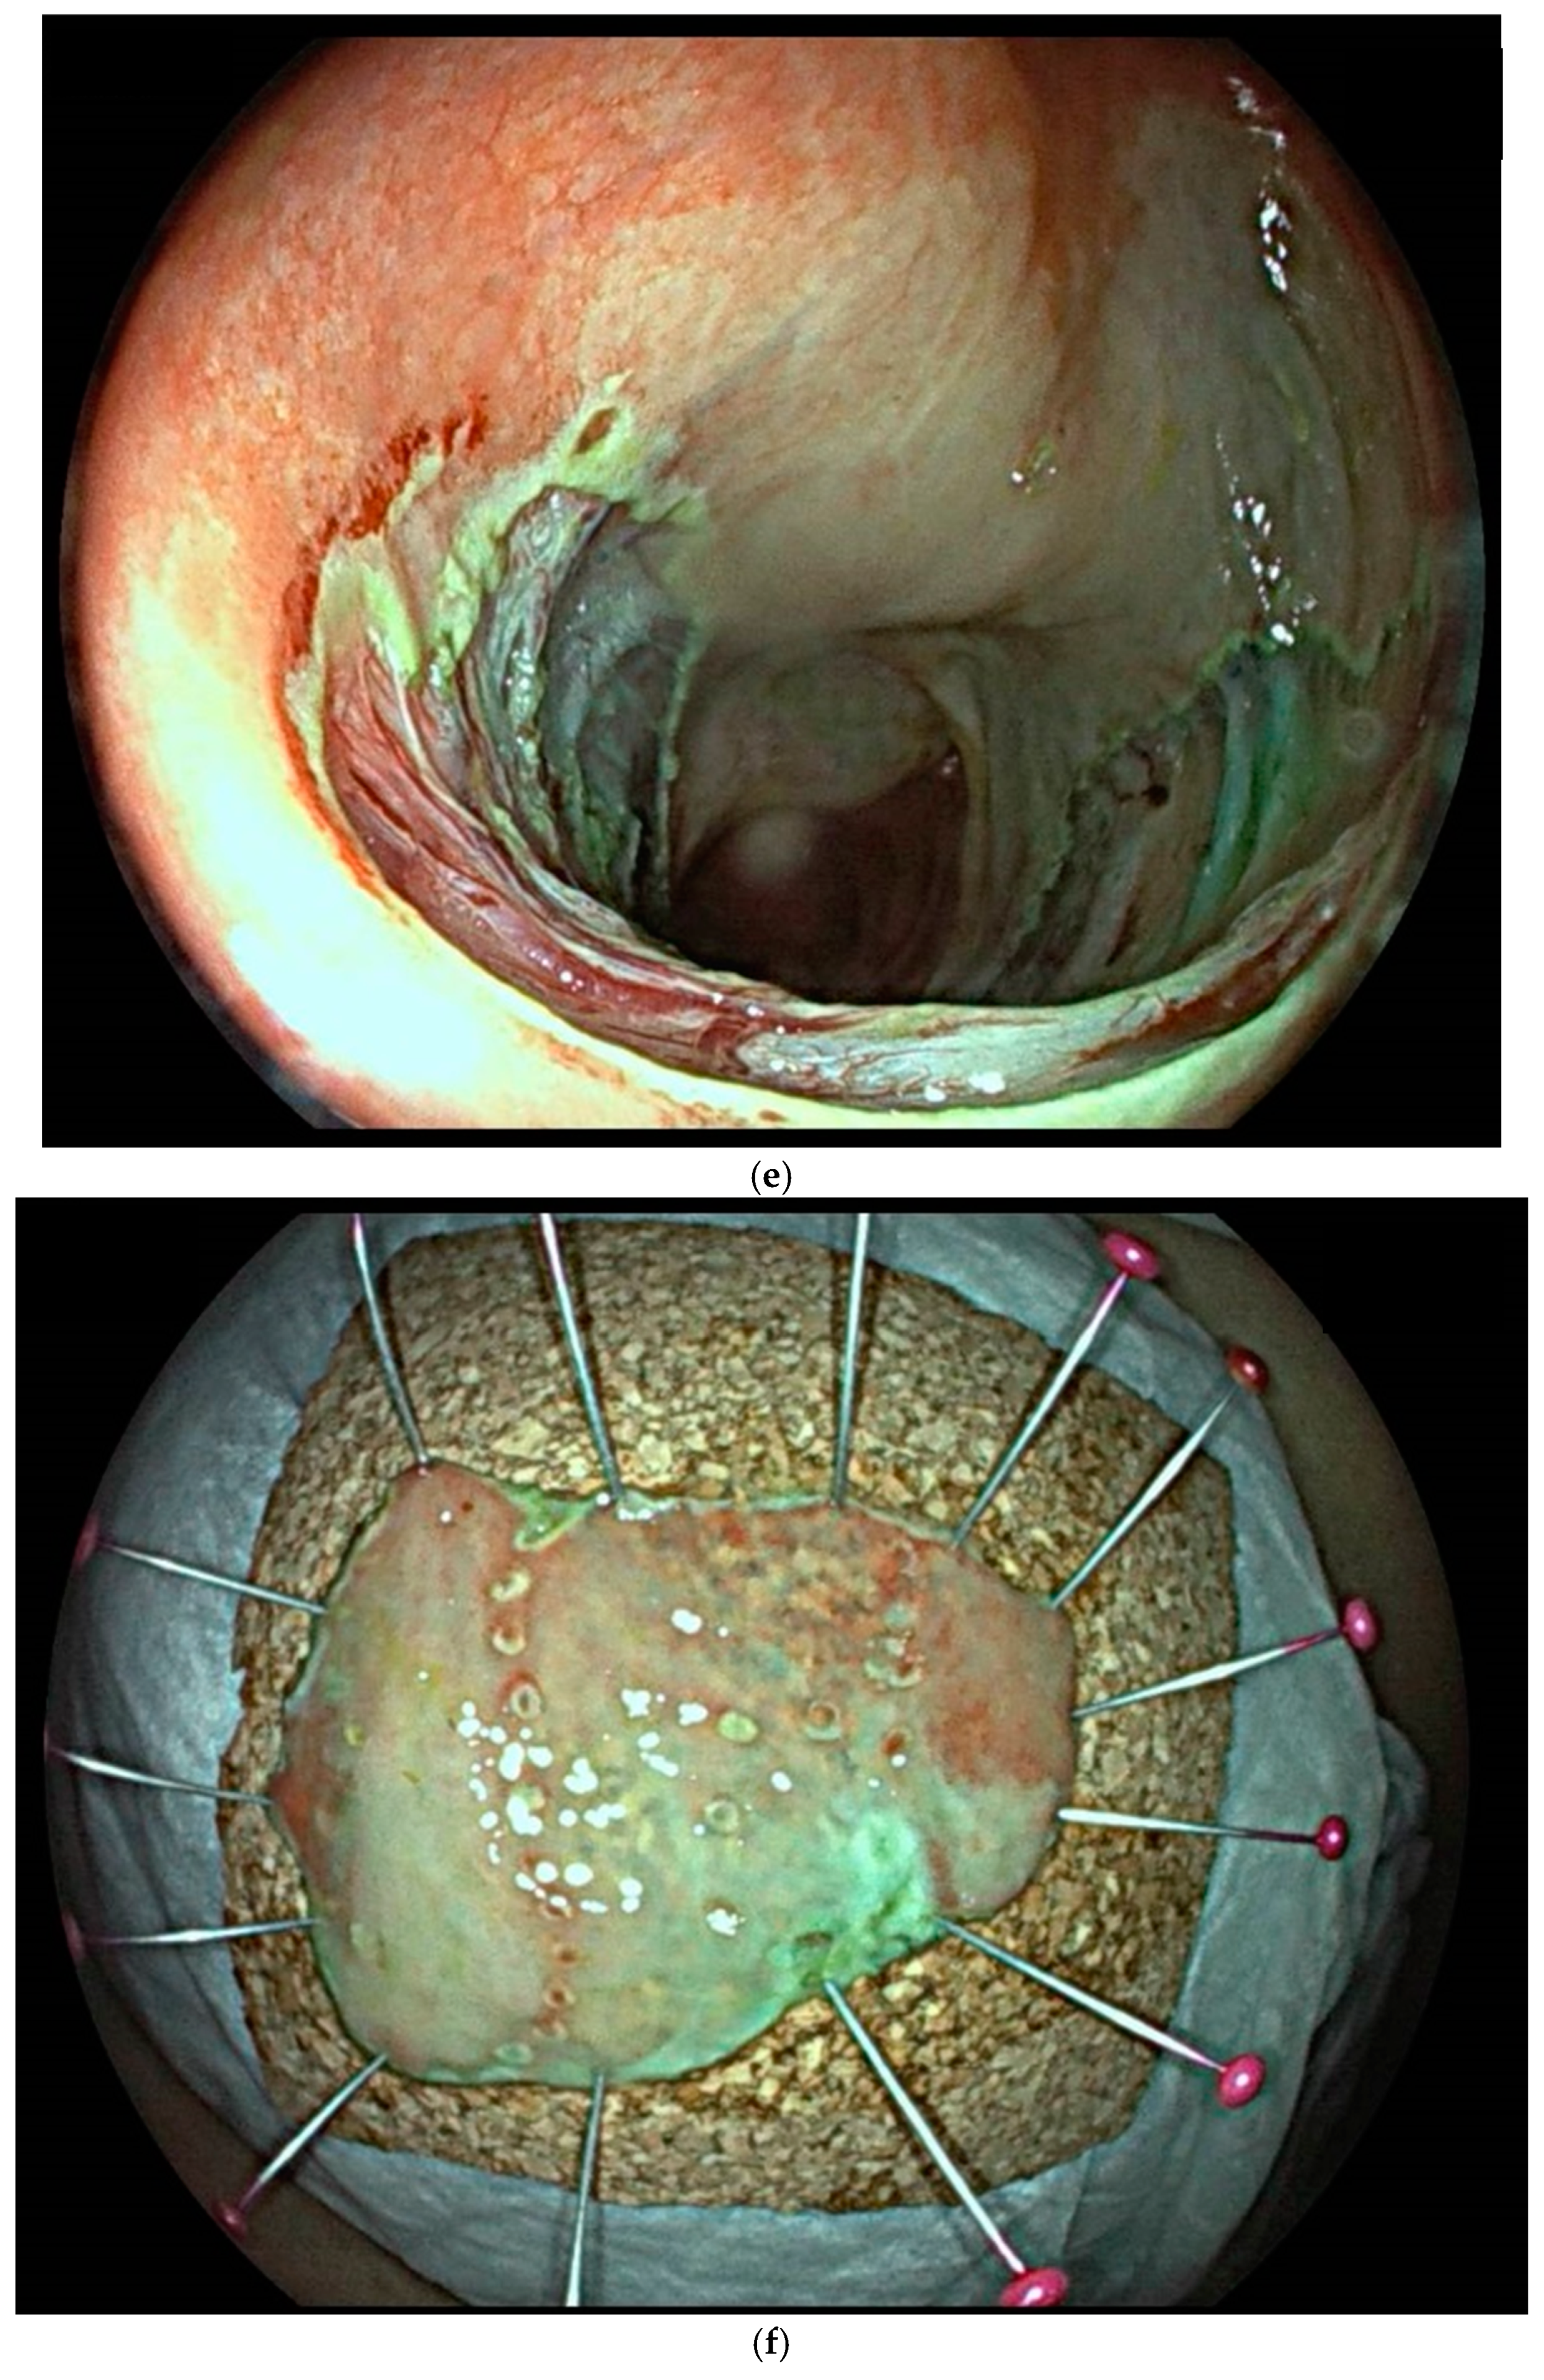

8. Endoscopic Resection Techniques

| Endoscopic submucosal dissection (ESD) is characterized by three steps: fluid injection into the submucosa in order to swell the lesion from the muscle layer and circumferential cutting of the mucosa surrounding the lesion, followed by dissection of the submucosal connective tissue beneath the lesion (standard technique). The major advantages of this technique in comparison with polypectomy or EMR include control of the resected size and shape, possible en bloc resection even in a large lesion and also resectability of the lesions in case of submucosal fibrosis. Disadvantages include the time-consuming procedure associated with a higher risk of complications (mainly bleeding and perforation) when compared with EMR [83]. | ![]() |